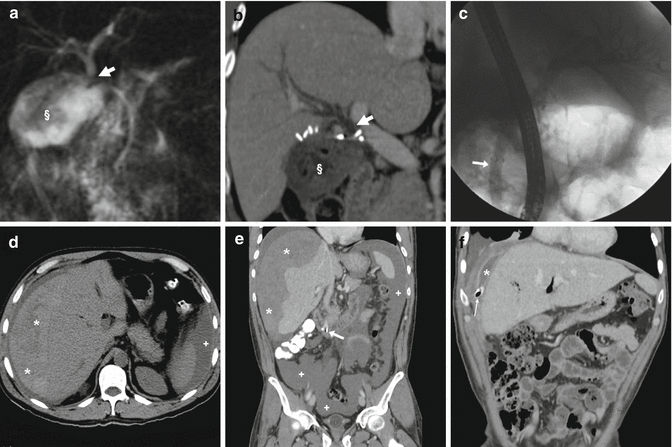

Photo Credit by: bing.com / after ercp stool findings endoscopic complications imaging retrograde

Photo Credit by: bing.com / ercp after stool findings imaging retrograde endoscopic complications

Photo Credit by: bing.com / after ercp stool complications imaging endoscopic findings retrograde